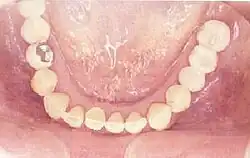

Eingegliederte Freiendbrücke 35–37 von okklusal (in der Aufsicht) -